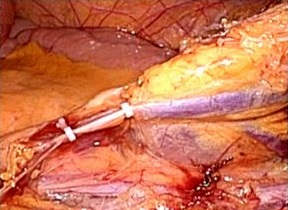

腹腔鏡手術で胆嚢の摘出と総胆管結石の摘除を同時に行います。胆嚢摘出後、十二指腸

上部総胆管を切開し、胆道鏡を用いて直視下に胆石を除去します。

採石後は胆道鏡で結石遺残のないことを確認します。その後胆管切開部を腹腔鏡下に

体内で結紮縫合を行い、閉鎖します。